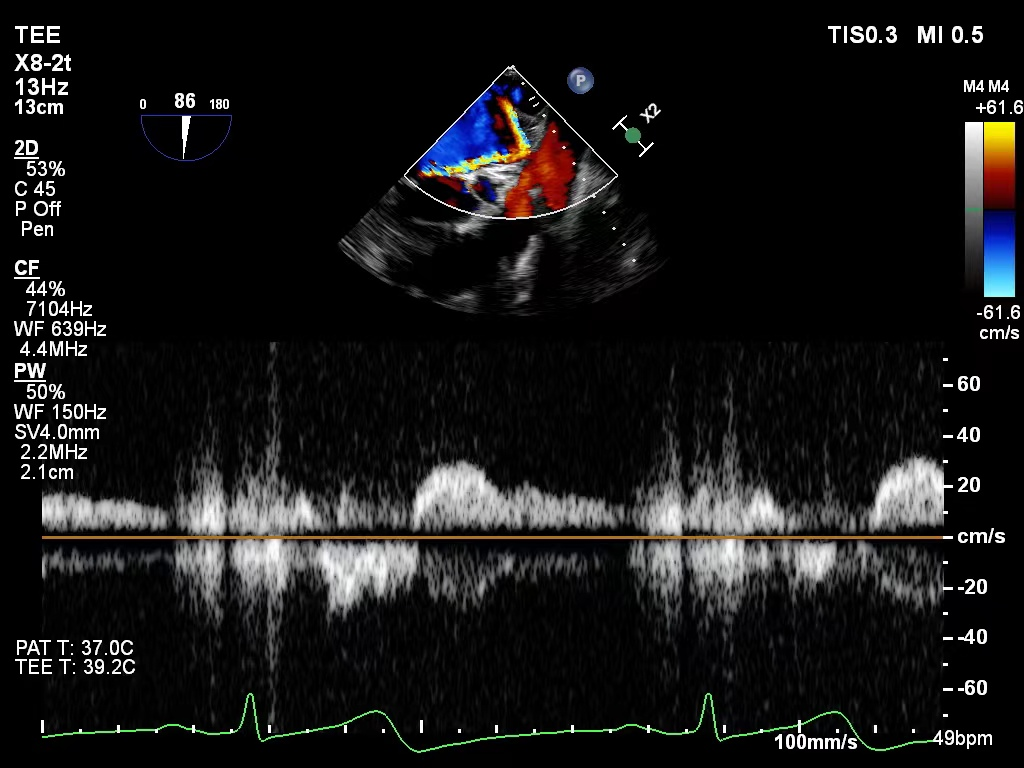

肺静脉血流频谱恢复正向